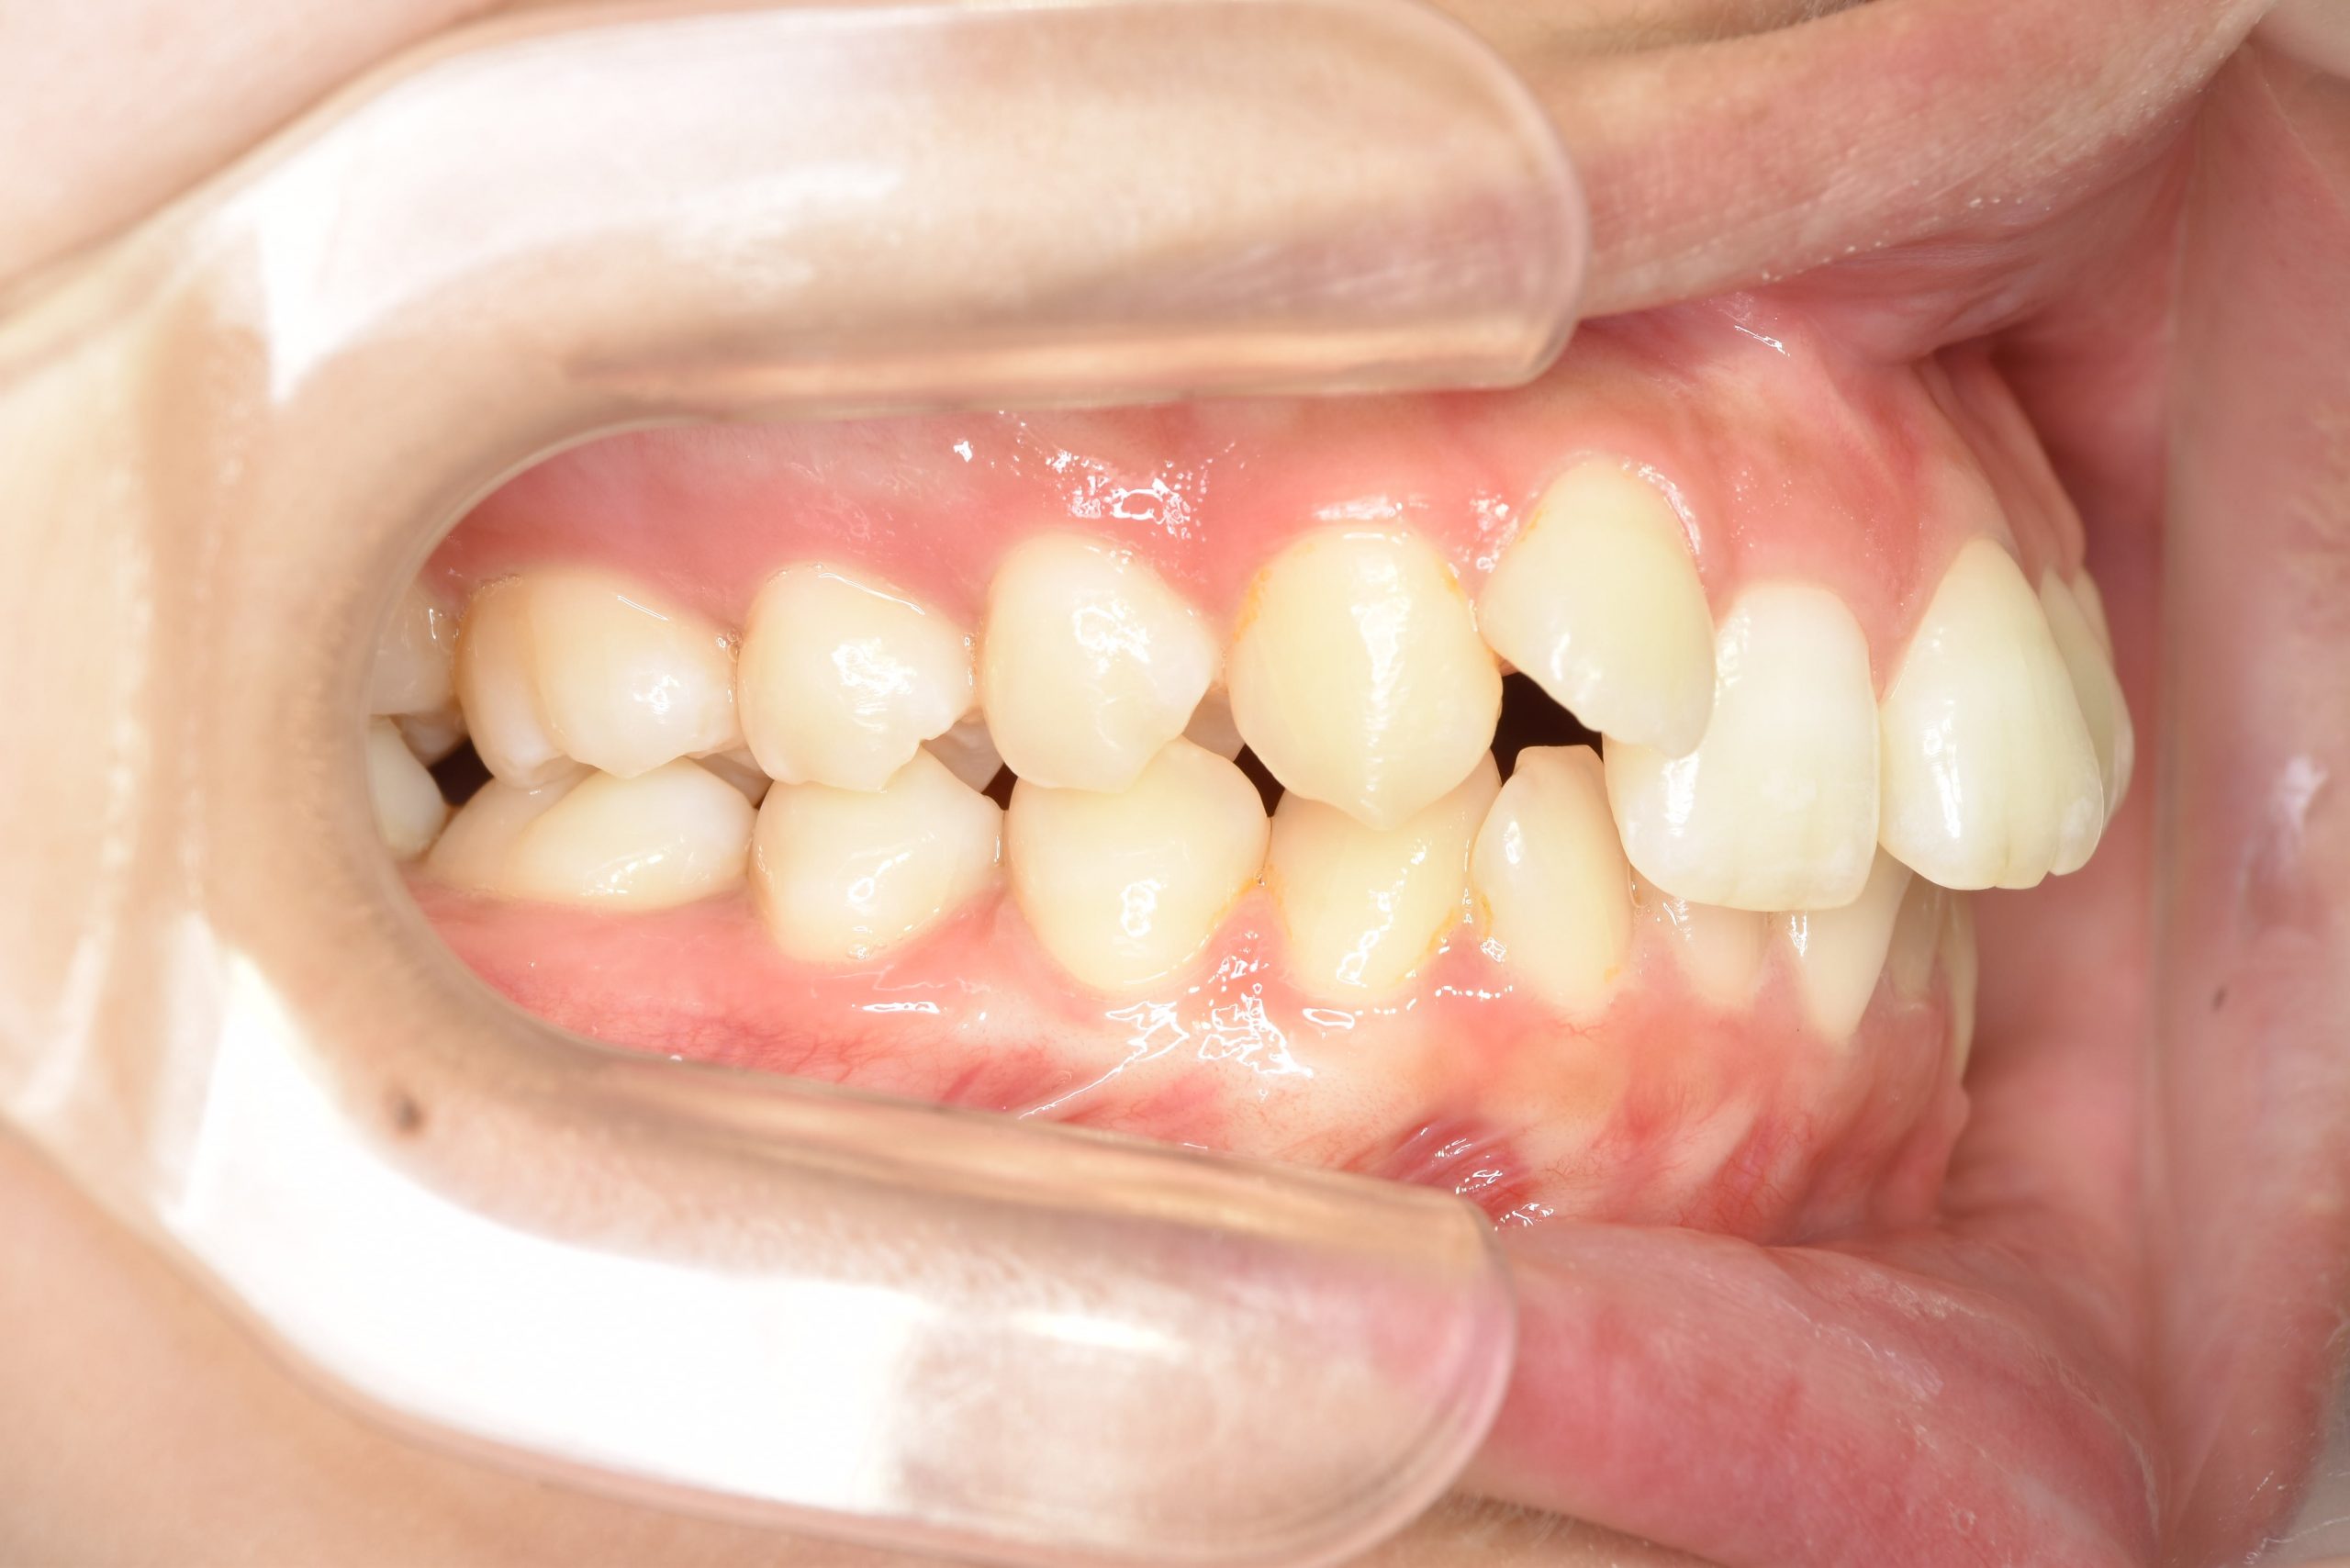

ビフォー

全顎ワイヤー矯正 症例_418

主訴 歯並びがガタガタ ※抜歯あり

施術内容 成人矯正1期治療

治癒期間 2年10か月間

費用 1,069,200円(税込)